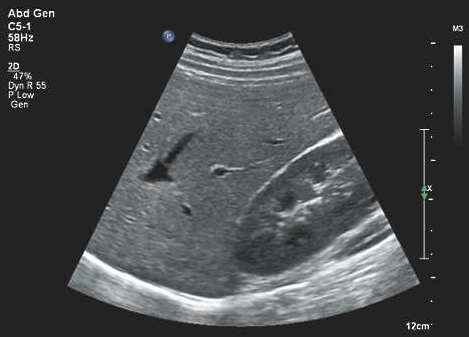

Abdominal sonography is a noninvasive imaging test that helps physicians diagnose and treat medical conditions by utilizing sound waves to visualize abdominal structures. An abdominal sonogram can help to diagnose a variety of conditions and to assess damage caused by illness. Doctors can also use abdominal sonography to guide them as they perform needle biopsies on abdominal organs. Abdominal sonography specifically focuses on structures in the upper abdomen.

An abdominal sonogram is performed using an ultrasound machine with a transducer and coupling gel. Coupling gel is placed on the area of interest between the skin and the transducer. The coupling gel provides a bridge between the transducer and the skin. This is necessary because ultrasound cannot pass through air or bone. The transducer generates ultrasound which is directed through the coupling gel into the body. As the ultrasound wave encounters structures within the body they are reflected back toward the transducer. These echoes are then sent to the ultrasound machine as electrical signals which are then converted to an image and displayed on the monitor. These images can be recorded as digital motion clips or as still images. Due to the real time nature of sonography blood flow, blood vessels, bowel movement, and movement of internal organs from breathing can be visualized.

Patients are referred for abdominal sonograms for various reasons including: abdominal pain, abnormal lab results, and enlarged abdominal organs. An abdominal ultrasound documents the abdominal organs and other structures in the upper abdomen such as the liver, gallbladder, pancreas, kidneys, spleen, aorta, inferior vena cava, and urinary bladder.